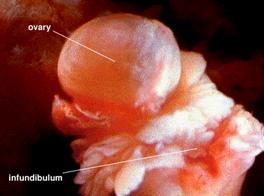

Fertilizarea are loc in tubul fallopian; aici se intalneste ovulul cu spermatozoidul. Contractiile ritmice ale tubului ajuta sperma sa se intalneasca cu ovulul. Rezulta zigotul, care mai ramane aici inca trei zile pana va fi implantat in uter. In a 7-a zi, trofoblastul se ataseaza de peretele uterin. Intre a10-a si a 12-a zi de sarcina, dar inaintea urmatorului ciclu menstrual, zigotul se ingroapa in mucoasa uterina, fara a se putea observa locul de intrare. In tot acest timp peretele uterin este pregatit de progesteronul secretat de corpul luteal.

Se diferentiaza degetele, articulatia genunchiului, gleznei si a cotului. La noua saptamani apar unghiile. Capul este cea mai voluminoasa parte a corpului. Barbia si gatul se separa de trunchi. Apar protruziile oculare, viitori ochi care sunt neacoperiti de pleoape. Apare morfologic diferentierea sexuala, testicule si ovare.